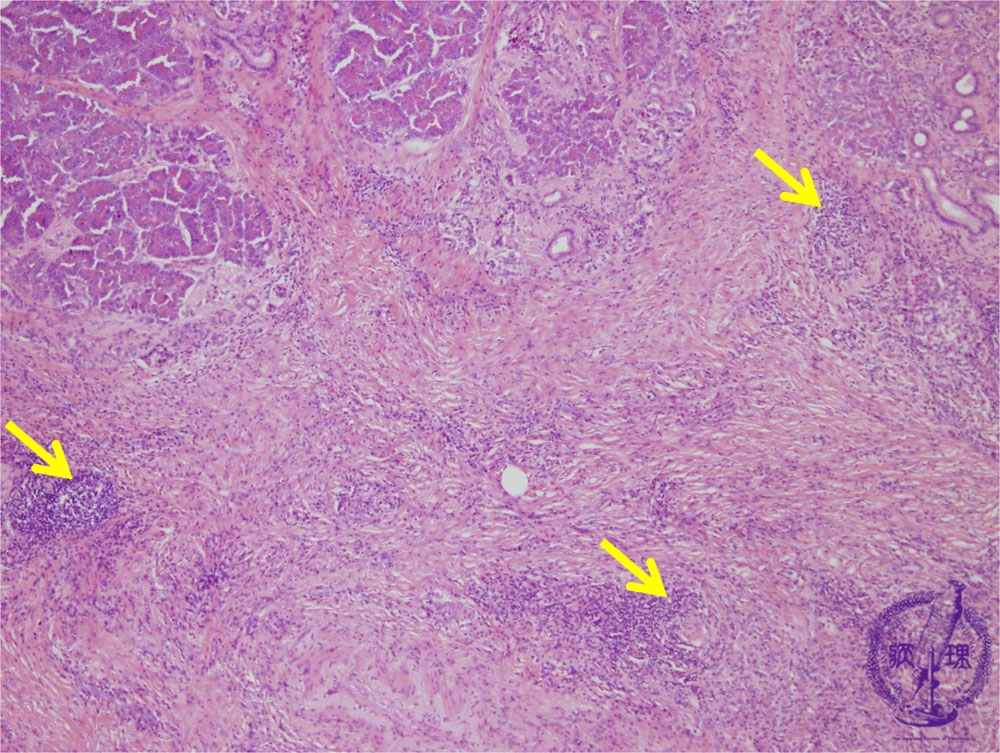

- (5)Chronic pancreatitis

Microscopic image(HE stain, low power): Advanced fibrosis is seen within the pancreatic parenchyma and interlobular spaces. Lymphoid follicles are seen forming amongst the fibrosis (arrows).